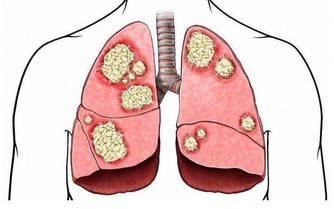

重油、重咸或重甜的內餡會造成血糖升高、增加血液黏稠度,

甚至誘發心絞痛和心肌梗塞,讓有慢性疾病的患者病情加重。